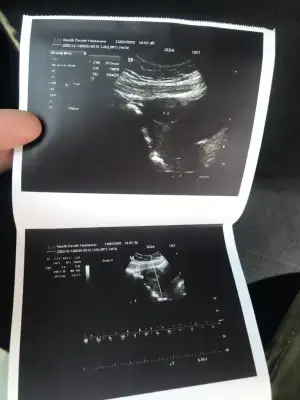

11 yada 12 hafta usg varsa bakabilirmiyim

Maalesef yok 10 haftalık ve kesenin fotoğrafı var 7 haftalık onları bi atiyim size11 yada 12 hafta usg varsa bakabilirmiyim![]()

Bunlara göre kız sanki nette değil usg ama kese kız yönündeMaalesef yok 10 haftalık ve kesenin fotoğrafı var 7 haftalık onları bi atiyim size![]()